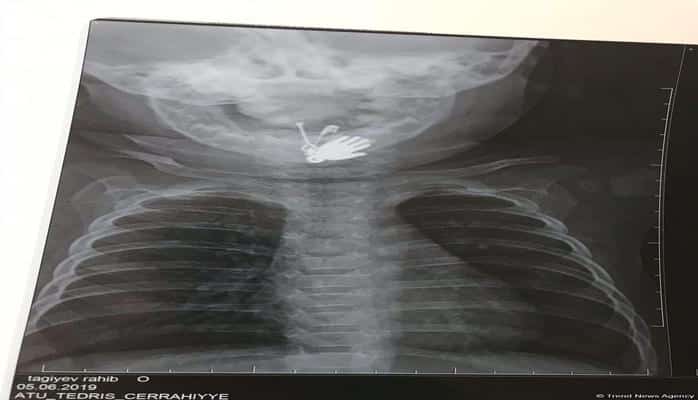

Azərbaycanda altı aylıq körpənin mədəsindən sancaq və digər cisimlər çıxarılıb.

Valideyn tərəfindən Bakıya xəstəxanaya çatdırılan uşağın mədəsində yad cismin olduğu məlum olub. Belə ki, altı aylıq körpə sancağı və üzərində olan digər əşyaları udub. Ə.F.Qarayev adına 2 saylı uşaq kliniki xəstəxanasında endoskopik üsul ilə körpənin mədəsindən həmin əşyalar çıxarılıb.